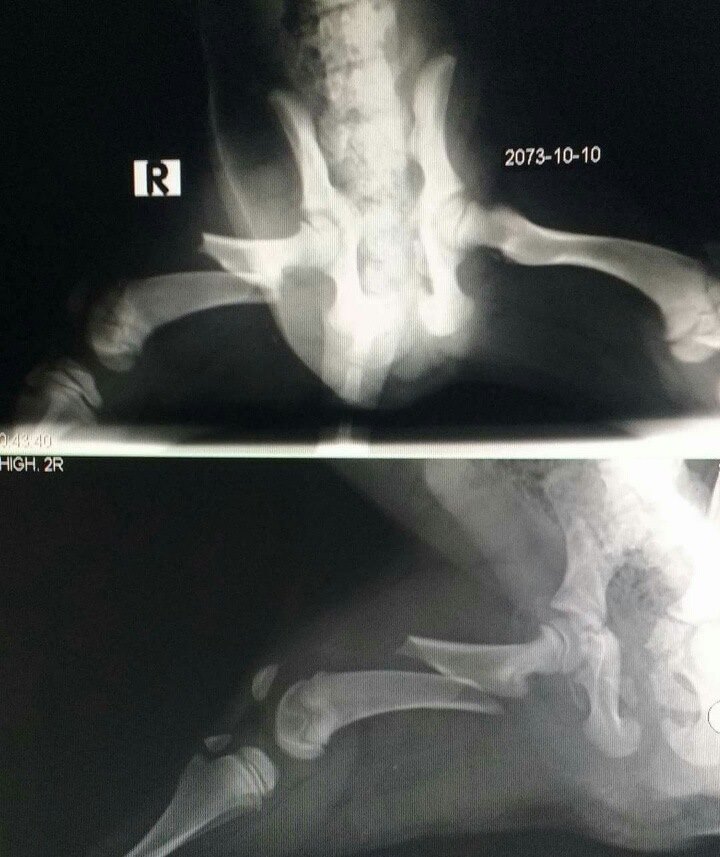

Have you ever imagined a life in a cold street and on top of that your leg is broken? It must be a nightmare. This little girl was rescued from a street of Baneshwor, Kathmandu once we got a rescue call from a kind person who saw her.

Her hind leg is fractured and now under our care. Why does anyone who drives doesn’t care about the life of animals? Why we humans just hate animals? What if it was a person who was hit by a vehicle? We need to STOP this legally, and we must have an animal law in Nepal.